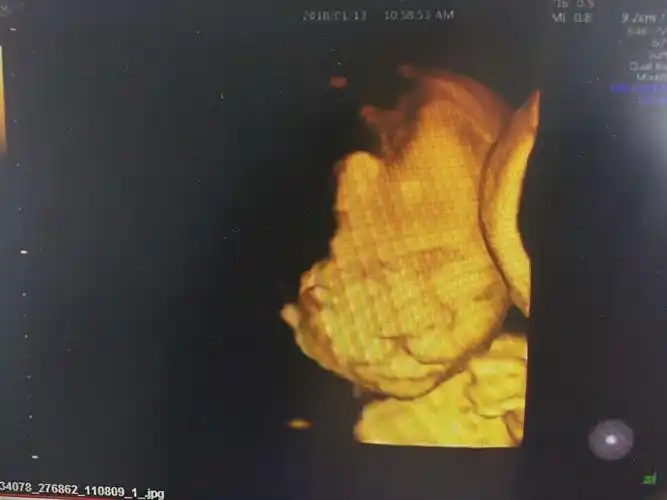

四维彩超唇腭裂

其它 扎赉特旗妇幼保健院彩超室 "gee8"四维彩超的引进,在妇产科领域

胎儿双侧唇裂四维成像图